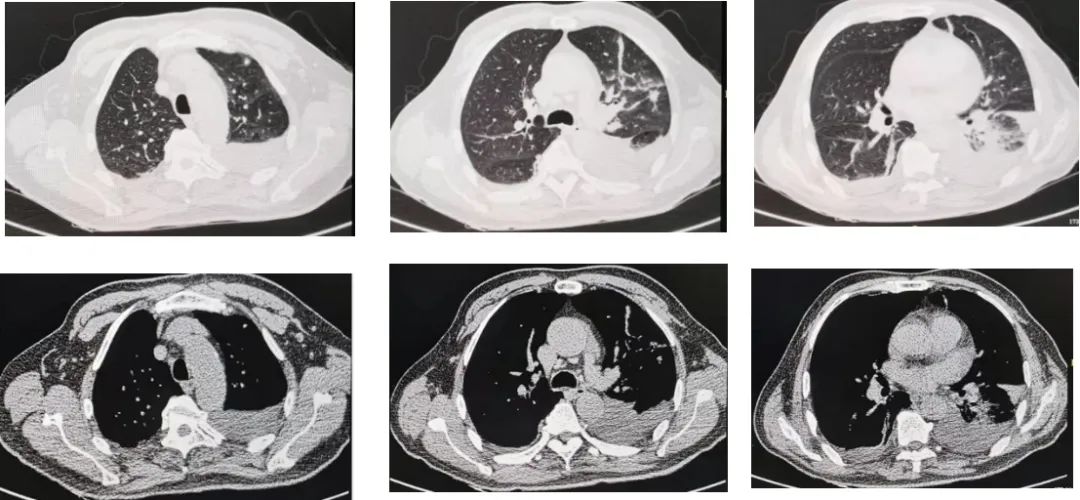

从排除中枢神经相关疾病,考虑周围神经病,再到怀疑肺部感染,进而得到验证,整个过程还算顺利,判断比较及时,未耽搁太多时间。既然「矛头」现已明确转向呼吸系统疾病,为了进一步明确患者的肺部病变,转入我科后立即对患者行胸部CT检查(图3)。

图3:胸部CT:双肺炎症,左侧为主,左侧胸腔少量积液,伴局部肺不张,心包少量积液。

为了解肺炎影像学变化情况,我们复查了胸部CT(图6、图7)。

图6:6月24日胸部CT

图7:7月6日复查胸部CT,显示双肺炎症、双侧胸腔积液较前进展。